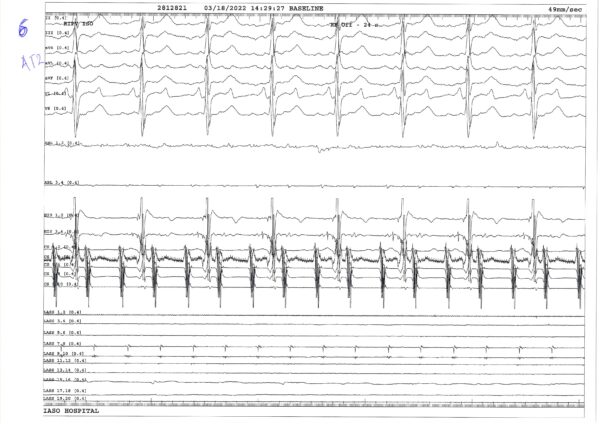

Ο ασθενής κατά την εισαγωγή του στο εργαστήριο βρισκόταν σε κολπική ταχυκαρδία με την κλινική μορφολογία. Ήταν ρυθμική κολπική ταχυκαρδία με αλληλουχία εγγύς πρός άπω στο στεφανιαίο κόλπο και μήκος κύκλου 231ms (ΑΤ1) (Καταγραφή 1). Η δοκιμασία παράσυρσης που έγινε από τον κοιλοτριγλωχινικό ισθμό ήταν αρνητική, με πολύ μεγαλύτερο μεταβηματοδοτικό διάστημα από το μήκος κύκλου (Καταγραφή 2). Με τη χρήση θηκαριού διαφραγματοστομίας (Preface, Biosense Webster) και βελόνας BRK, έγινε η διαφραγματική παρακέντηση σε κεντρική θέση του ωοειδούς τρήματος. Η παρακέντηση του ωοειδούς τρήματος έγινε υπό ηχοκαρδιογραφική καθοδήγηση με χρήση του καθετήρα ενδοκαρδιακού υπερήχου ViewFlex™ Xtra (Abbott). Διαμέσου της διενεργηθείσης διαφραγματοστομίας και του θηκαριού Preface εισήχθη στον αριστερό κόλπο ο κυκλοτερής καθετήρας και με μακρυ πηδαλιουχούμενο θηκάρι (Agilis, Abbott) εισήχθη στον αριστερό κόλπο ο καθετήρας κατάλυσης.

Με διαδοχική μετακίνηση των καθετήρων, αρχικά, κατασκευάστηκε το τρισδιάστατο μοντέλο του αριστερού κόλπου και των ΠΦ (Εικόνες, CD). Από τον έλεγχο που έγινε εντός του άντρου των ΠΦ διαπιστώθηκε επανασύνδεση στις δεξιές ΠΦ και έγινε απομόνωση της δεξιάς άνω ΠΦ με σημειακή εφαρμογή ενέργειας στην περιοχή μεταξύ των δεξιών ΠΦ (Καταγραφή 3). Επί της κολπικής ταχυκαρδίας (ΑΤ 1) έγινε χάρτης διέγερσης. Διαπιστώθηκε ότι επρόκειτο για κύκλωμα περί την οροφή με ανιούσα φορά στο οπίσθιο τοίχωμα και διέλευση του ερεθίσματος από κενό στην δεξιά πλευρά της προηγούμενης γραμμικής βλάβης οροφής (Video 1). H δοκιμασία παράσυρσης που έγινε από το οπίσθιο τοίχωμα ήταν θετική (Καταγραφή 3). Για την κατάλυση της κολπικής ταχυκαρδίας (ΑΤ 1) χορηγήθηκε ενέργεια στο κενό της γραμμής οροφής, όπου είχαμε αργή διέλευση του ερεθίσματος, με αποτέλεσμα την άμεση μετάπτωση της ταχυκαρδίας σε άλλη μορφή με άπω προς εγγύς αλληλουχία στο στεφανιαίο κόλπο και μήκος κύκλου 330 ms (ΑΤ 2) (Καταγραφές 5,6). Επίσης διαπιστώθηκε μικρής έκτασης επανασύνδεση στην δεξιά κάτω ΠΦ που συμπληρώθηκε (Καταγραφή 6). Με την μετακίνηση των καθετήρων έγινε νέος χάρτης διέγερσης για την ΑΤ 2 που έδειξε κύκλωμα μικροεπανεισόδου στην ακρολοφία μεταξύ των αριστερών ΠΦ και του ωτίου (Video 2A– 2B). Στην περιοχή αυτή καταγράφονταν κατακερματισμένο κολπικό ηλεκτρόγραμμα το οποίο σε χρονική διάρκεια κάλυπτε >30% του μήκους κύκλου (Καταγραφή 7). Η κατάλυση στην περιοχή αυτή τερμάτισε άμεσα την ταχυκαρδία (Καταγραφή 8) και συνεχίστηκε μέχρι την απομείωση των δυναμικών.